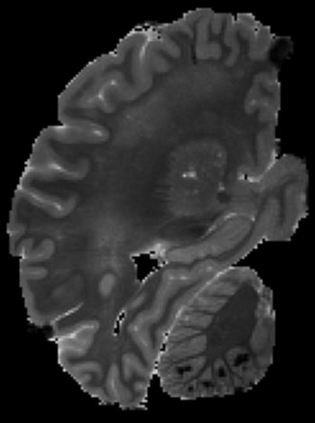

In neuroimaging, MRI tissue properties characterize underlying neurobiology, provide quantitative biomarkers for neurological disease detection and analysis, and can be used to synthesize arbitrary MRI contrasts. Estimating tissue properties from a single scan session using a protocol available on all clinical scanners promises to reduce scan time and cost, enable quantitative analysis in routine clinical scans and provide scan-independent biomarkers of disease. However, existing tissue properties estimation methods - most often $\mathbf{T_1}$ relaxation, $\mathbf{T_2^*}$ relaxation, and proton density ($\mathbf{PD}$) - require data from multiple scan sessions and cannot estimate all properties from a single clinically available MRI protocol such as the multiecho MRI scan. In addition, the widespread use of non-standard acquisition parameters across clinical imaging sites require estimation methods that can generalize across varying scanner parameters. However, existing learning methods are acquisition protocol specific and cannot estimate from heterogenous clinical data from different imaging sites. In this work we propose an unsupervised deep-learning strategy that employs MRI physics to estimate all three tissue properties from a single multiecho MRI scan session, and generalizes across varying acquisition parameters. The proposed strategy optimizes accurate synthesis of new MRI contrasts from estimated latent tissue properties, enabling unsupervised training, we also employ random acquisition parameters during training to achieve acquisition generalization. We provide the first demonstration of estimating all tissue properties from a single multiecho scan session. We demonstrate improved accuracy and generalizability for tissue property estimation and MRI synthesis.